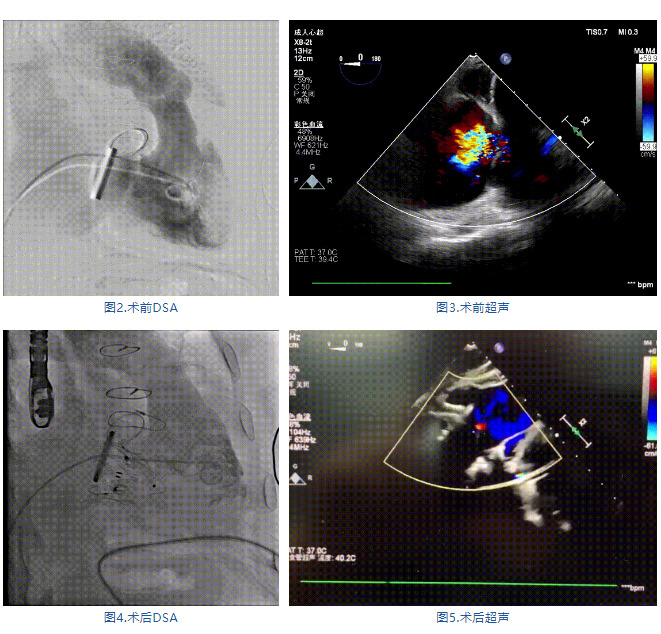

手術在全麻狀態(tài)下進行,郭惠明教授團隊采用經右側頸靜脈入路的方式送入輸送器進入體內,并在TEE和DSA的指引下進行。在輸送器進入右室后釋放室間隔錨定裝置,旋轉輸送器,使得錨定裝置對準室間隔面;而后釋放前瓣夾持件,確定夾持件位于右室側釋放LuX-Valve Plus人工瓣膜盤片,再使用DSA和超聲確認盤片是否位于右房側,同時調整瓣膜的同軸性。緊接著在DSA和超聲的監(jiān)視下調整室間隔錨定件貼合室間隔,釋放室間隔錨定裝置。再次確認瓣膜的穩(wěn)定性和同軸性后,將輸送器撤出體內,最終完成LuX-Valve Plus人工瓣膜植入(圖2-5),手術獲得圓滿成功?;颊咴谑中g室即刻拔除氣管插管,術后超聲提示LuX-Valve Plus人工三尖瓣瓣膜同軸性良好,瓣架固定牢靠,無反流和瓣周漏。